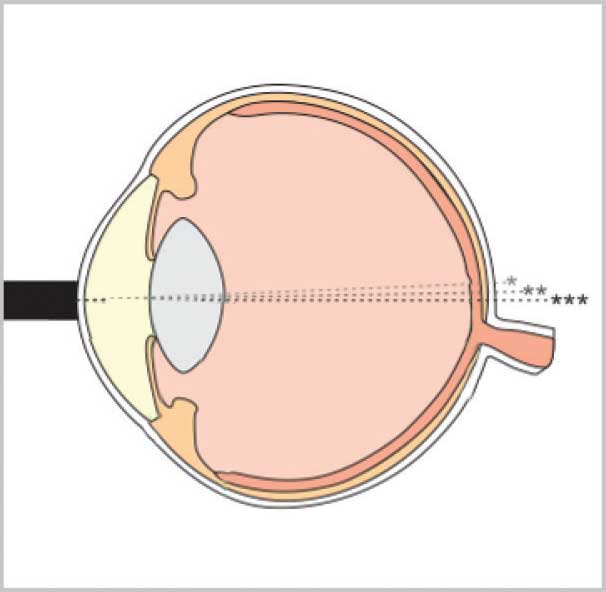

The innovative Flex A-Scan offers clinicians an unmatched level of usability and accuracy. Unique measurement guidance features assist in achieving optimal measurement values. These features allow the user to focus on application technique while the device’s software performs real-time waveform analysis and provides immediate feedback to the user.

The DGH Software supports multiple IOL formulas, including post-refractive formulas. A-Scan measurements can be taken via direct corneal contact or via water immersion method (Prager Shell® included).

A-Scan Measurement Features

A unique grading algorithm automatically ranks the probe’s alignment along the axis of measurement. Alignment ranking is immediate, with each qualified measurement assigned a 1-star, 2-star or 3-star rank (3-star representing best alignment). Aided by the audible feedback, the user can adjust the probe’s contact angle during a procedure, correcting misalignments and thereby optimizing measurement.

Unique compression lockout feature for use during contact measurements. When enabled, compression lockout will stop the system from measuring waveforms which show indications of corneal compression. Audible tones are provided to guide the user in adjusting contact pressure and aid in alleviating flattening of the cornea. The compression sensitivity level is adjustable to aid in obtaining contact measurements with minimum compression.